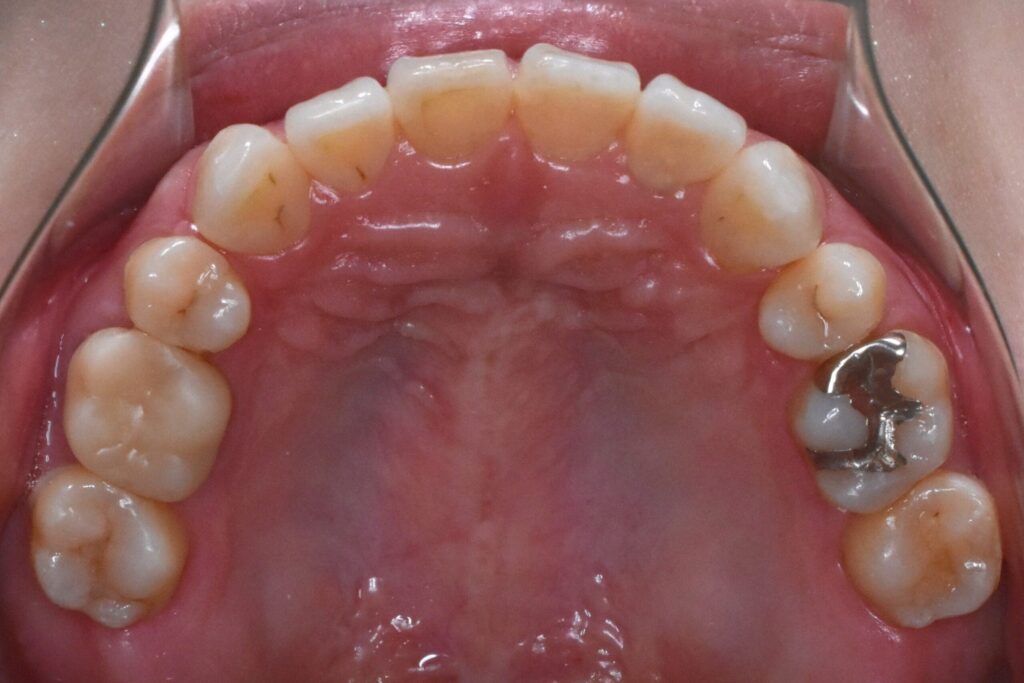

Before